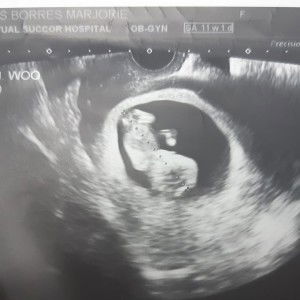

Preggers